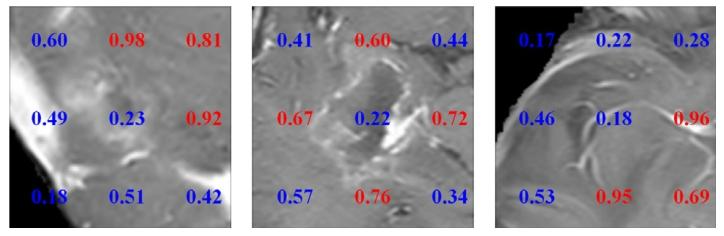

Fig. 7. Visualization result of the proposed method. Estimated probability of HRAprediction for each patch. Red and blue numbers represent areas of HRA or non-HRA,respectively

图7 所提方法的可视化结果。每个图像块(patch)的高风险复发区域(HRA)预测概率。红色数字和蓝色数字分别代表高风险复发区域和非高风险复发区域。